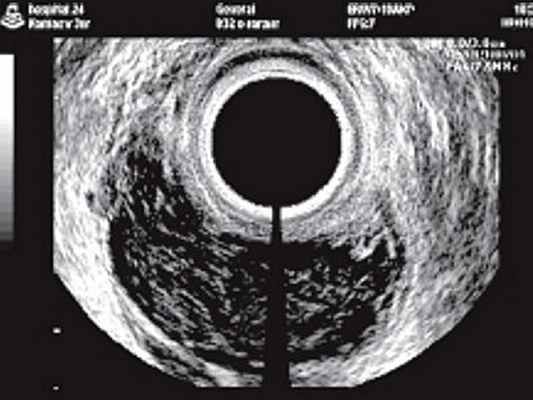

В результате клинического обследования вынесено заключение: объемное образование в полости малого таза. В процесс вовлечена прямая кишка. Выражено ее сужение. Так как слизистая оболочка прямой кишки не была поражена, был исключен диагноз рака кишки, и считалось необходимым провести дифференциальный диагноз между саркомой, лимфомой и воспалительной опухолью, т.е. индуративным хроническим парапроктитом. В объеме дополнительных исследований выполнено эндо ректальное ультразвуковое исследование с последующим контролем над эффективностью проводимого лечения. Исследование выполнялось на УЗ-сканере SА-5500 компании MEDISON c использованием полостного высокочастотного механического датчика с номинальной рабочей частотой 7,5 МГц. Пациент в положении на левом боку с согнутыми в тазобедренных и коленных суставах ногами.

а) Опухоль в стенке прямой кишки и клетчатке на уровне предстательной железы. Слева от опухоли в клетчатке увеличенный гипоэхогенный лимфатический узел.

б) Опухоль на уровне семенных пузырьков. Изображение перевернуто, цифры 6 и 12 обозначают положение датчика по отношению к передней (12 часов) и задней (6 часов) стенкам прямой кишки.

в) Опухоль на уровне семенных пузырьков.

1 - стенка кишки; 2 - опухоль; 3 - параректальная клетчатка; 4 - надкостница крестца; 5 - слизистый слой кишки.

При трансректальном ультразвуковом исследовании (ТРУЗИ) датчик был проведен на 15 см от анального канала, были осмотрены стенки прямой кишки и параректальная клетчатка. Установлено, что анальные сфинктеры обычной структуры. На высоте 4 см от ануса преимущественно по задней стенке определялась опухоль (рис. 1а) 5,2х4,0х7,0 см низкой эхогенности с мелкоточечными множественными гиперэхогенными включения ми. Контуры опухоли неровные, границы нечеткие. Слизистая оболочка прямой кишки в зоне опухоли не изменена, представлена гиперэхогенным слоем. Отмечалась выраженная инфильтрация опухолью параректальной клетчатки, доходящая практически до надкостницы крестца (рис. 1 б, в). Наряду с этим в непосредственной близости от основной опухоли в параректальной клетчатке определялись гипоэхогенные образования с неровными контурами, которые были расценены как депозиты опухоли (см. рис. 1а). Кроме того, в параректальной клетчатке вы явлены два гипоэхогенных образования округлой формы с ровными четкими контура ми 1,4х1,3х1,4 и 1,0х1,0х1,1 см, которые представляли собой увеличенные лимфатические узлы. Дано заключение о наличии опухоли прямой кишки, исходящей из ее внутренних слоев, прорастающей до надкостницы крестца.

Спустя 1,5 года после начала терапии при контрольном ТРУЗИ стенки прямой кишки имели обычное строение, элементов опухоли не определялось (рис. 2).

В выполненном исследовании основной отличительной особенностью данной опухоли от аденокарциномы прямой кишки явилась визуализация неизмененного гиперэхогенного слизистого слоя между поверхностью датчика и самой опухолью.

При неизмененной слизистой оболочке прямой кишки и наличии опухолевидного образования в толще ее стенки, кроме лимфосаркомы следует думать о такой патологии, как лейомиосаркома, липома, ангиома, гемангиоэпителиома прямой кишки, воспалительные заболевания. Для липом и сосудистых опухолей характерна более высокая эхогенность, чем при лимфосаркоме. Для лейомиосаркомы характерна низкая эхогенность, но более четкие и ровные контуры [20]. Острые парапроктиты (рис. 3) в стадии инфильтрации имеют более высокую эхогенность и звукопроводимость, неоднородную внутреннюю структуру, а после формирования капсулы они становятся практически анэхогенными, четко отграниченными от окружающих тканей.

Рис. 3. Задний подковообразный острый парапроктит. В отличие от лимфосаркомы имеются четкие контуры образования, расположенного кзади от стенок прямой кишки, хорошо видны плотные стенки, дистальное усиление эхосигнала.

Результаты гистологического исследования дают основания предположить, что эта опухоль возникла из лимфатического узла параректальной клетчатки и распространилась за его пределы. В связи с тем, что рост опухоли происходил в сторону просвета прямой кишки, создавалось ложное впечатление о возникновении патологического процесса из ее стенки. Однако выявление при ТРУЗИ и ректороманоскопии нормальной слизистой позволило исключить первичное поражение этого органа.

В заключение следует отметить, что правильный диагноз лимфомы прямой кишки представляет довольно сложную задачу. Однако при интенсивном опухолевом росте в параректальной клетчатке с поражением стенок прямой кишки, низкой эхогенности опухоли при одновременном отсутствии поражения со стороны слизистой можно вы сказать предположение о наличии лимфо саркомы прямой кишки.